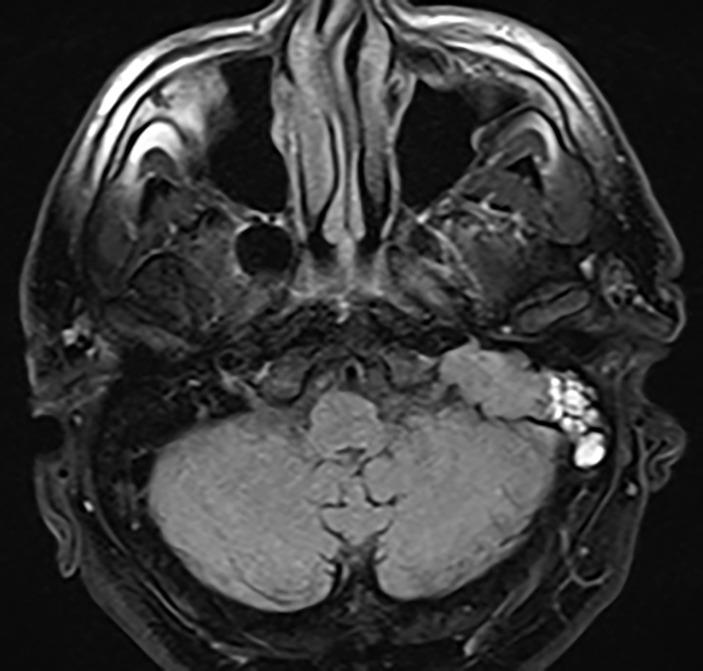

The vast majority of chondrosarcomas of the skull (CS) are located at the skull base and represent locally aggressive malignant tumors that account for 0.15% of all intracranial neoplasms. Complete surgical resection with wide surgical margins is currently the main treatment strategy, but can be hard to achieve due to the complex anatomy of the head and neck. The jugular foramen, situated in the floor of the posterior fossa and posterolaterally to the petro-occipital suture, is a remarkably rare location for CS. A case of primary CS of the jugular foramen in a 65-year-old patient is reported, presenting with otalgia, pulsatile tinnitus, and mild hearing loss in the left ear, accompanied by peripheral facial nerve paresis. Radiographic imaging showed a mass in the left mastoid, middle ear and jugular fossa with bone destruction of the jugular fossa and mastoid, while magnetic resonance imaging showed additional involvement of the petroclival fissure, hypoglossal canal, jugular bulb, and sigmoid sinus. The tumor was resected with wide margins through a Fisch infratemporal fossa approach type A, followed by radiotherapy. Results of the immunophenotyping along with histological features primarily matched moderately differentiated chondrosarcoma. The patient is recurrence free at 6 months after treatment. Middle ear discharge with facial palsy as a first manifestation of the CS has not been described to date. The unique localization, treatment details and histopathologic data are relevant in expanding the current level of knowledge on the subject.

绝大多数颅骨软骨肉瘤(CS)位于颅底,是具有局部侵袭性的恶性肿瘤,占所有颅内肿瘤的0.15%。目前,采用宽手术切缘的完整手术切除是主要治疗策略,但由于头颈部解剖结构复杂,难以实现。颈静脉孔位于后颅窝底部、岩枕缝后外侧,是CS极为罕见的发病部位。本文报告了一例65岁患者的颈静脉孔原发性CS,表现为耳痛、搏动性耳鸣和左耳轻度听力损失,并伴有周围性面神经麻痹。影像学检查显示左侧乳突、中耳和颈静脉窝有肿块,颈静脉窝和乳突骨质破坏,而磁共振成像显示岩斜裂、舌下神经管、颈静脉球和乙状窦也有受累。通过Fisch A型颞下窝入路对肿瘤进行了宽切缘切除,并进行了放疗。免疫表型分析结果与组织学特征主要符合中度分化软骨肉瘤。患者在治疗后6个月无复发。以中耳流脓和面神经麻痹作为CS首发表现的情况迄今尚未见报道。该独特的发病部位、治疗细节和组织病理学数据对于扩展当前对该疾病的认识水平具有重要意义。